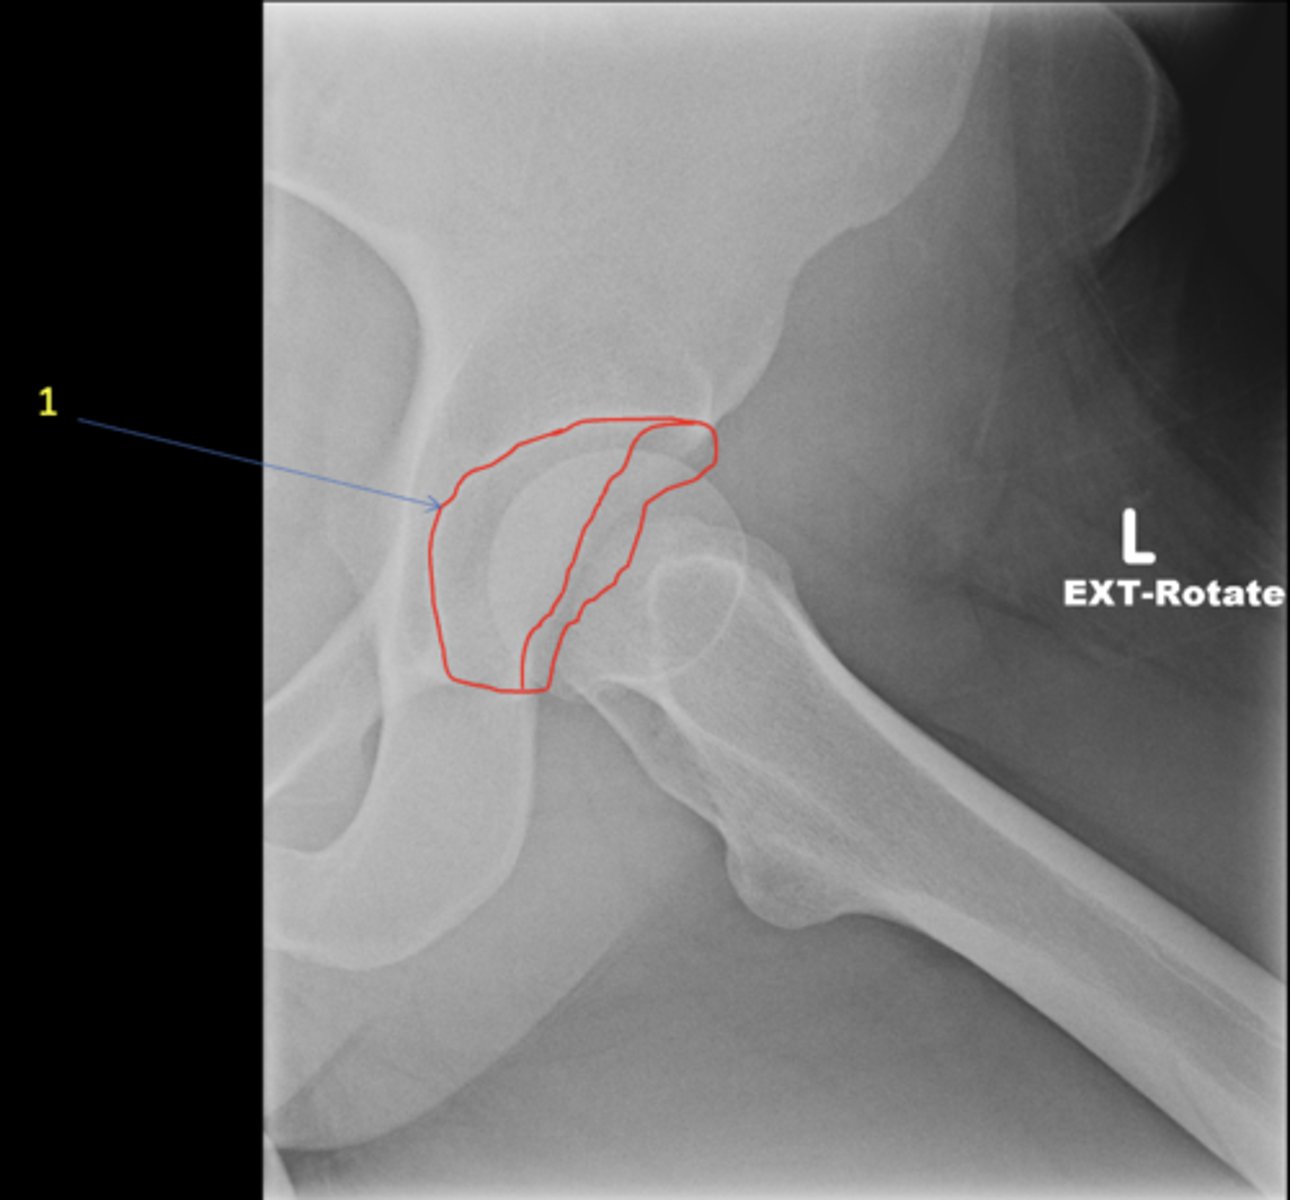

Left frog-leg hip

View?

<p>View?</p>

43

New cards

Acetabulum

ID 1

<p>ID 1</p>